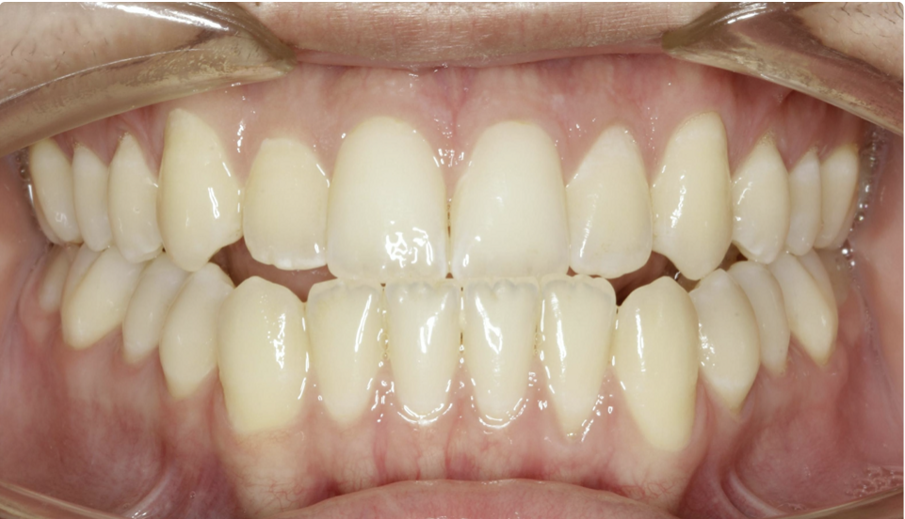

A great solution for Class III patients in need of mandibular distalisation for profile aesthetics and dental function is buccal shelf TADs. This solution allows for noncompliance correction of Class III cases with decreased compensation of the maxillary arch (Figs. 42–45, beginning of treatment). For these cases, a 2 × 12 mm Ortho Bone Screw is placed mesial to teeth #47 and #37 into the buccal shelf of the mandibular body. If the patient has mandibular third molars, then they are extracted right before the TADs are placed once in the stainless-steel wires.

Once the patient has progressed to stainless-steel wires, buccal shelf TADs are placed. A mandibular pre-posted stainless-steel wire is used, and a VectorTAS NiTi closing spring is placed from the buccal shelf TAD to the post (Fig. 46). Once the Class III has been corrected, a steel ligature is used to retain the Class III malocclusion while finishing and detailing are completed (Figs. 47–51, end of treatment).

Fig. 47

Fig. 48

Fig. 49

Fig. 50

Fig. 51